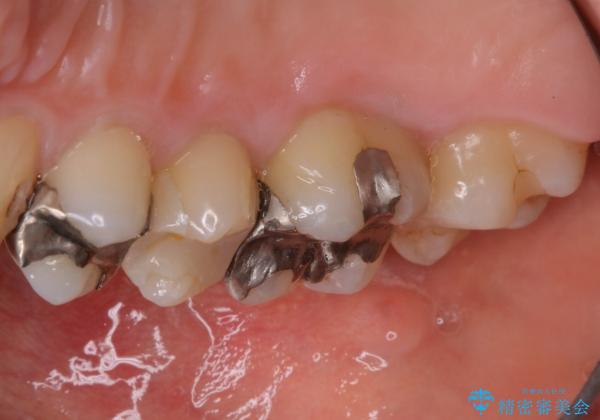

歯の表面に、茶色く色が残っている所がありますが、これは詰め物の変色の所と、虫歯になっている所です。以前に、CR(コンポジットレジン)による虫歯治療がされています。

CRは経年的劣化や、着色してしまうことがあります。PMTCでクリーニングを行うと、古いCRが目立つことがあるため、気になる際は詰め替えを行います。

茶色くなっている部分が、着色なのか、劣化なのか、虫歯によるものなのかは判別が難しいことがあります。そのため、定期的にPMTCを行うことで状態の確認が的確に行えます。